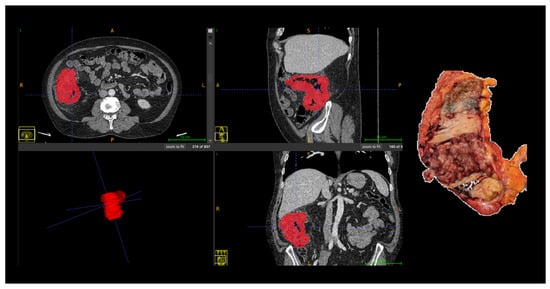

Machine Learning Radiomics in Computed Tomography for Prediction of Tumor and Nodal Stages in Colorectal Cancer

by Lara de Souza Moreno, Tony Alexandre Medeiros da Silva, Mayra Veloso Ayrimoraes Soares, João Luiz Azevedo de Carvalho and Fabio Pittella-Silva

Background/Objectives: Accurate preoperative TN staging is essential for guiding surgical and adjuvant treatment decisions in colorectal cancer (CRC), yet conventional imaging still faces limitations in reliably distinguishing early from advanced disease. This study aimed to evaluate whether CT-based radiomics combined with machine learning can noninvasively predict both tumor (T) and nodal (N) stages of CRC, and to identify which feature groups most contribute to each task. Methods: Fifty-three patients (55 tumors) with histologically confirmed CRC who underwent preoperative contrast-enhanced CT were retrospectively analyzed. A total of 107 radiomic features were extracted using PyRadiomics version 3.1.0, including shape, first-order, and texture features. Multiple preprocessing strategies—z-score normalization, PCA, and SMOTE—were tested across 11 machine learning classifiers. Results: For T staging, logistic regression using shape-based features achieved a mean sensitivity of 0.721, a specificity of 0.68, a balanced accuracy of 0.70, and an AUC of 0.751. For N staging, the AdaBoost model using texture-based features achieved a sensitivity of 0.742, a specificity of 0.622, a balanced accuracy of 0.682, and an AUC of 0.750. Shape features predominantly contributed to T prediction, while texture matrices drove N prediction, reflecting morphological and microstructural correlates of invasiveness and lymphatic dissemination. Conclusions: CT-based radiomics can quantitatively capture both morphological and textural patterns of tumor behavior, providing a noninvasive framework for preoperative TN staging in CRC. Full article